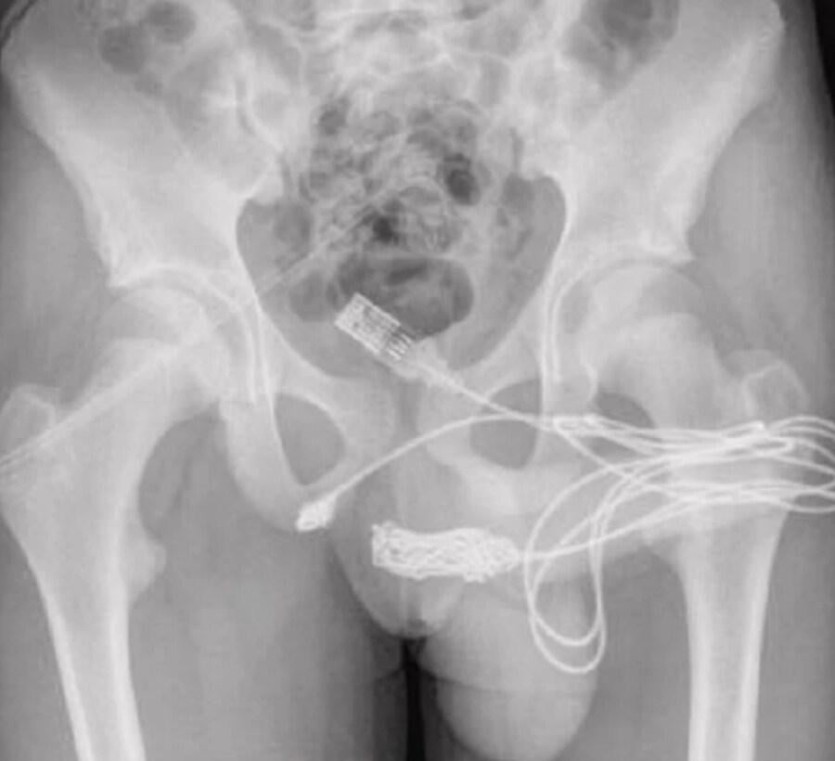

음경 길이 재려고 요도에'이것'집어넣은 15세 소년